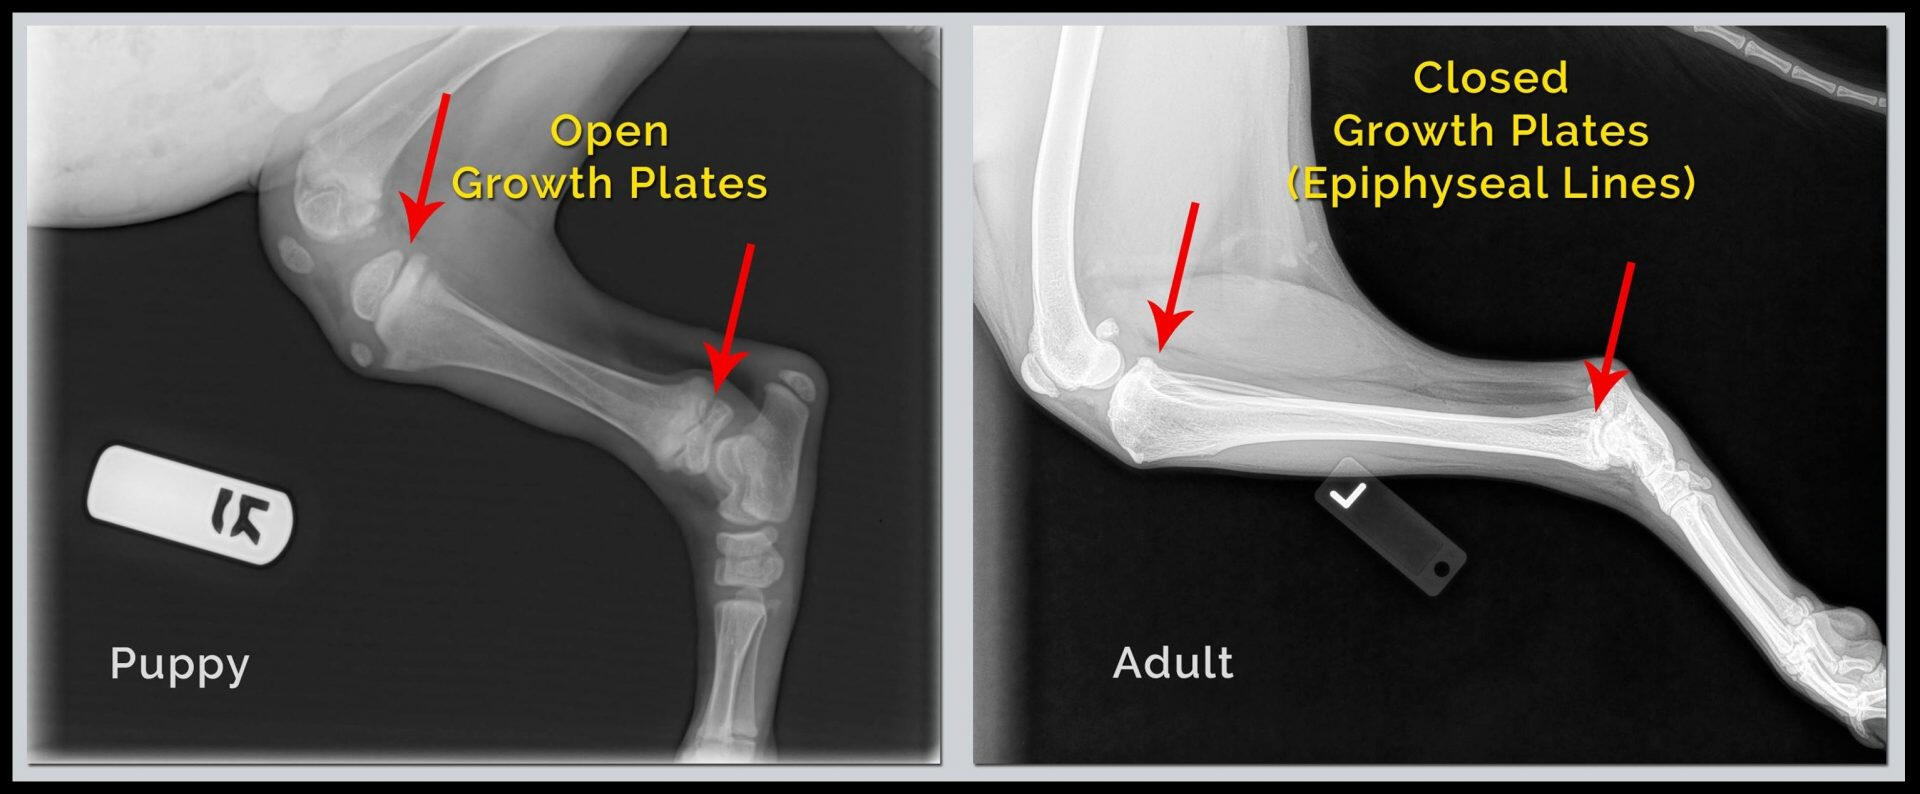

Regelmatig wordt ik benaderd door trotse baasjes met de vraag of zij met hun pup ook mee mogen wandelen. Mijn advies is altijd, te wachten totdat de pup minstens 1 jaar oud is omdat de wandelingen die ik organiseer meestal 2 uur duren en dat is voor jonge honden tot 1 jaar echt te lang. Ik zal proberen mijn advies te onderbouwen, de uiteindelijke beslissing ligt natuurlijk altijd bij de baasjes.WAAROM?Als je 8 tot 10 weken oude pup bij je komt wonen, is het skelet nog niet volledig is uitgehard. Botten en gewrichten van pups ontwikkelen zich gemiddeld nog totdat ze 18-24 maanden oud zijn. (zie ook foto “sluiten groeiplaten honden (gemiddeld in maanden”)

Maar de oorzaak van deze waggelgang is wel gelegen in het feit de delen van de botten nog uit een zachtere substantie bestaan, de zogenaamde groeiplaten of -schijven, en dat het de spieren, pezen, ligamenten en huidbedekking zijn, die voor de stabiliteit van het lichaam moeten zorgen.

Het zijn dus nog niet de sterke botten die het lichaam dragen! Op röntgenfoto’s is het ontbreken van stevige botten goed te zien aangezien hier alleen harde botstructuur zichtbaar wordt.